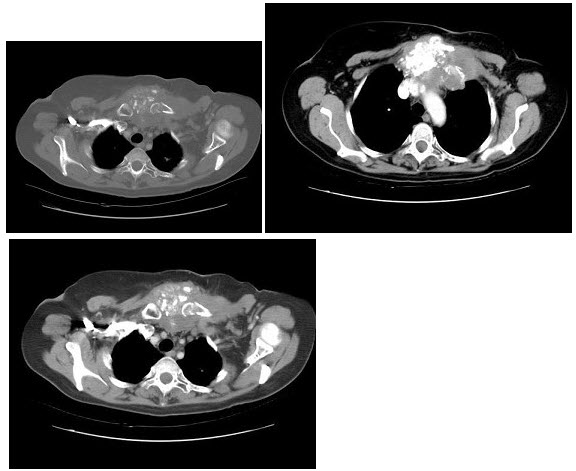

[单选题]女,56岁,乳腺癌手术后,未行化疗,结合CT图像,最可能的诊断是()A .肺转移癌B .肺结核C .间质性肺炎D .肺结节病E .肺曲菌病

[单选题]患者女,56岁,乳腺癌手术后,未行化疗,结合CT图像,最可能的诊断是A.肺转移瘤B.肺结核C.间质性肺炎D.肺结节病E.肺曲菌病

[单选题]女,56岁,乳腺癌手术后,未行化疗,结合CT图像,选择最可能的诊断是()A . 肺转移癌B . 肺结核C . 间质性肺炎D . 肺结节病E . 肺曲菌病